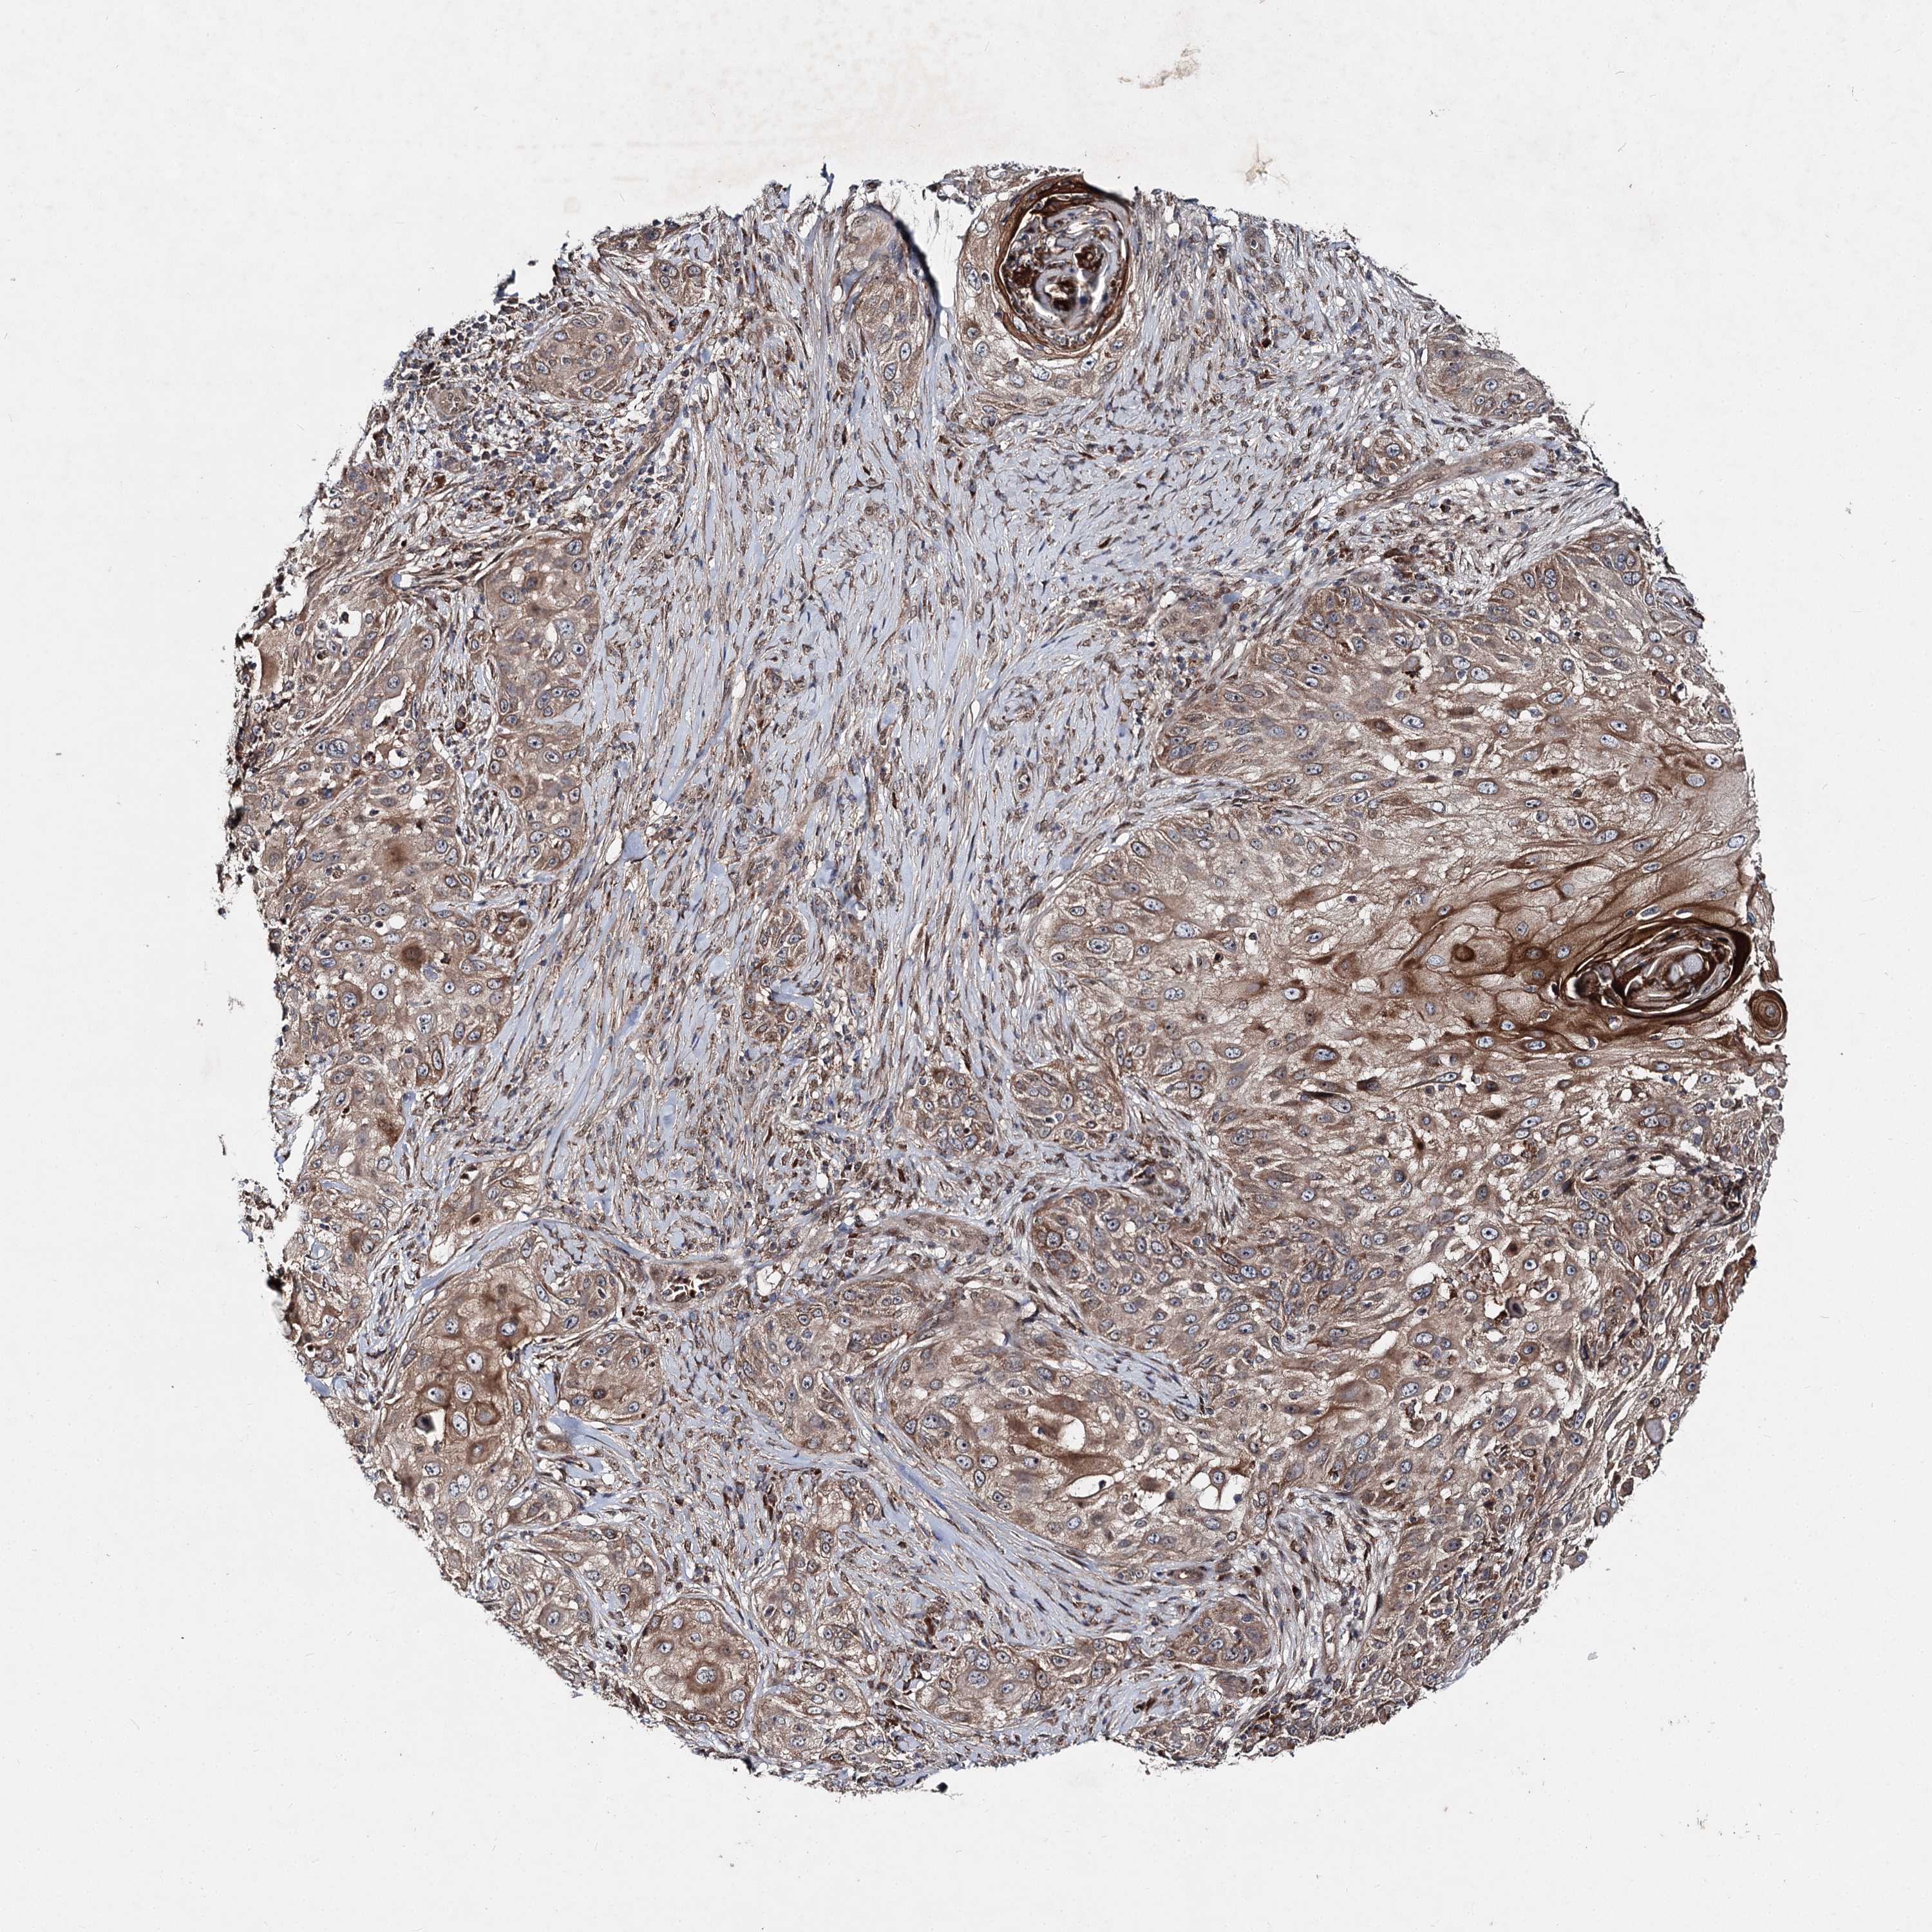

Basal cell and squamous cell cancer

SKIN CANCER - Protein expressioni

A mouse-over function shows sample information and annotation data. Click on an image to view it in a full screen mode. Samples can be filtered based on level of antibody staining by selecting one or several of the following categories: high, medium, low and not detected. The assay and annotation is described here.

Antibody stainingi

Antibody staining in the annotated cell types in the current human tissue is reported as not detected, low, medium, or high, based on conventional immunohistochemistry profiling in selected tissues. This score is based on the combination of the staining intensity and fraction of stained cells.

Each image is clickable and will lead to virtual microscopy that enables deeper exploration of all samples and also displays staining intensity scores, fraction scores and subcellular localization as well as patient and tissue information for each sample.

Antibody HPA038694

Antibody HPA038695

Staining

High

Medium

Low

Not detected

Intensity

Strong

Moderate

Weak

Negative

Quantity

>75%

75%-25%

<25%

None

Location

Nuclear

Cytoplasmic/membranous

Cytoplasmic/membranous,nuclear

Squamous cell carcinoma, NOS